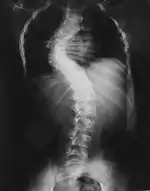

Проявления нейрофиброматоза I типа часто начинаются со сколиоза (искривления позвоночника), затем возникают трудности в обучении, проблемы со зрением и эпилепсия.

Для выраженного нейрофиброматоза характерна деформация позвоночника в виде сколиоза, возможны краевые дефекты тел позвонков, их суставных и поперечных отростков, расширение межпозвоночных отверстий и эрозии их краёв, узуры нижних краёв задних отделов рёбер, вызванные давлением нейрофиброматозных узлов[36].

| Сколиоз | ||||